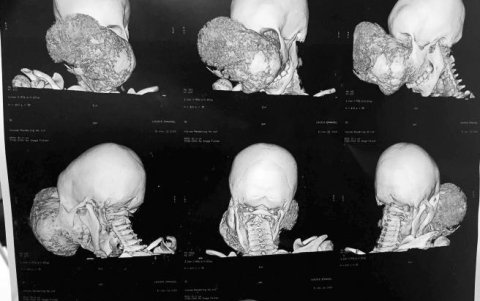

TAC con distintas imágenes del tumor.

Tras estudiar durante cerca de dos semanas este "caso raro e infrecuente", ya que "no hay muchos tumores que lleguen a este tamaño", se planeó la cirugía y fue intervenido en dos ocasiones y con una diferencia entre ambas de ocho días, la última hace poco más de una semana.

Durante la primera intervención, que duró cerca de diez horas, se le quitó todo el maxilar, la zona entre las órbitas oculares, el paladar y una parte del interior de la boca, que fue reconstruido tras extirpar el tumor.

La segunda cirugía, también de cerca de diez horas de duración, se centró en hacer la parte intracreaneal, para quitar la base anterior y media del cráneo y reconstruírselo con parte de sus propias costillas.